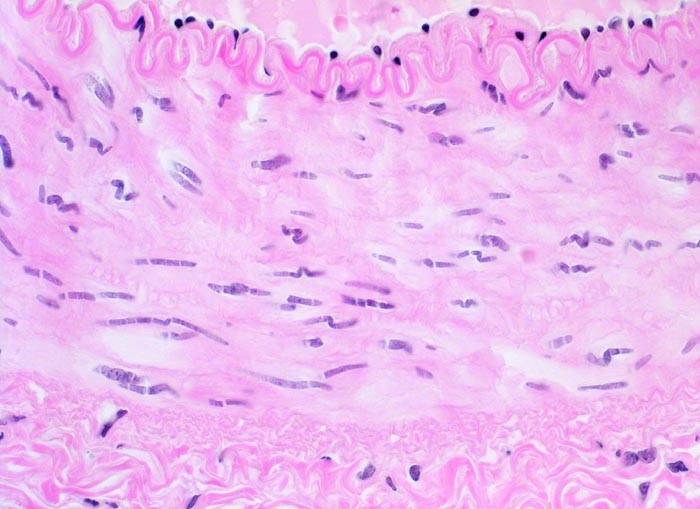

Abgeheilte Vaskulitis: Segmentaler oder kompletter Verlust der elastischen Fasern in mittleren und grossen Gefässen assoziiert mit zellarmer Vernarbung der Gefässwand.

• Fragmentierung, Abblassung und herdförmig Zerstörung der Lamina elastica interna über längere Strecken (EvG Färbung).